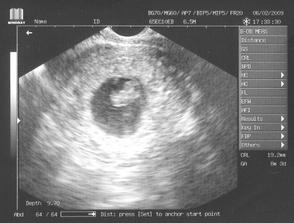

14.1.09 - kontrola u nového gyn., potvrzeno 🙂 miminko máme a první utz - další kontrola 6.2.

6.2.09 - potvrzené srdíčko, měříme 19,3mm a jsme v 8tt+3 ... za 3 týdny jdeme na testy, snad dopadnou dobře